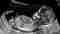

Vascular Doppler: Insightful Vascular Health Assessment

Unveiling the Power of Vascular Doppler Technology

At Texas Imaging & Labs, we bring you to the forefront of vascular health assessment with our state-of-the-art Vascular Doppler services. Our advanced technology, coupled with expert care, ensures a comprehensive evaluation of your vascular well-being. Explore the precision of our services tailored to meet your specific needs: